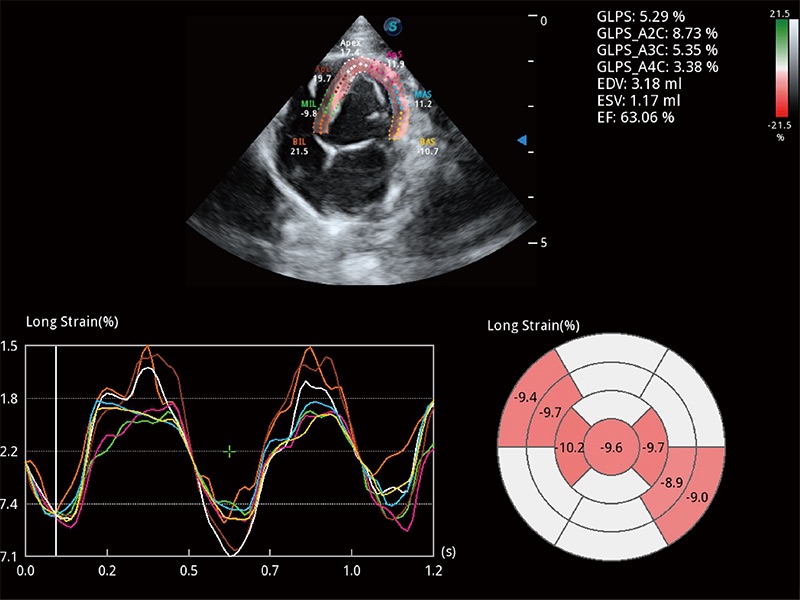

通過心肌識別技術(shù)與二維斑點追蹤技術(shù)相結(jié)合,對心臟的超聲圖像進行量化分析。計算心肌17個節(jié)段的應(yīng)變、應(yīng)變率、速度、位移等,并通過牛眼圖的形式進行呈現(xiàn)。